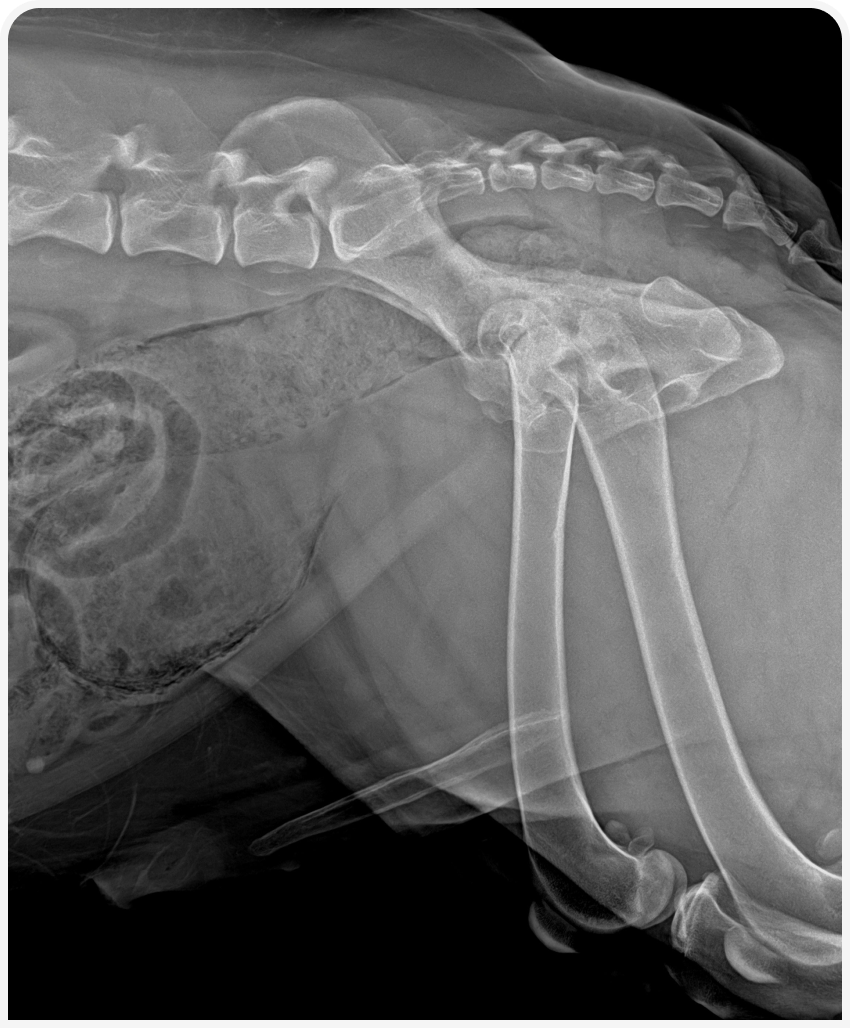

В ходе обследования мы можем обнаружить локальное скопление газа в стенке мочевого пузыря. А также столкнуться с трудностями в визуализации мочевого пузыря из-за тотального присутствия газа в стенках мочевого пузыря и артефактов изображения. Присутствие газа также может быть выявлено в уретре, из редка может быть выявлен газ в почечных лоханках и в тканях простаты у кобелей.

Рисунок 1. Рентгеновский снимок брюшной полости и области уретры в боковой проекции пациента с эмфизематозным циститом.

Интактный кобель 8 лет, вес 50 кг доставлен в клинику в связи с макрогематурией.

Осмотр не примечателен, пациент стабилен. Месяцем ранее проведена кастрации в связи с доброкачественной кистозной гиперплазией простаты. Выявлено присутствие газа в стенке мочевого пузыря и уретры. Исключен сахарный диабет, протеинурия ранее не выявлялась.